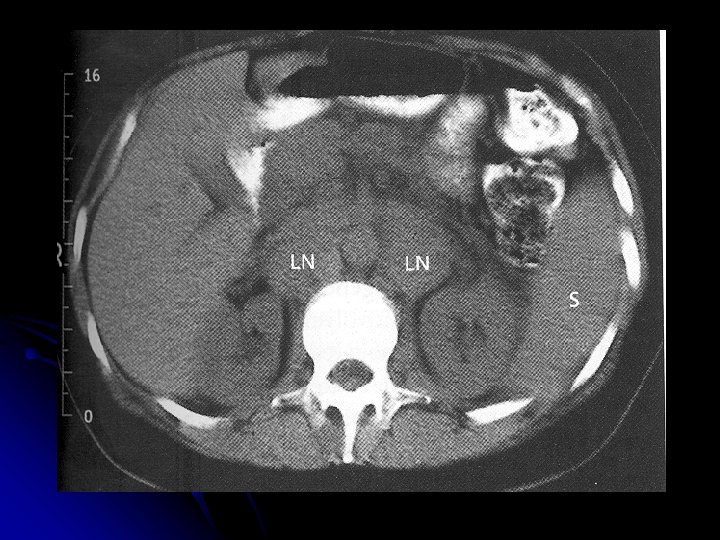

Investigations l l l l l CBP : Anemia ( normochromic / normocytic), eosinophilia, neutrophilia, lymphopenia ESR -raised LFT- (liver infil / obs at porta hepatis) RFT- prior to treatment Urate , Ca, LDH - adverse prognosis CXR- mediastinal mass CT thorax / abdomen / pelvis-for staging Other: Gallium scan, PET, Lymphangiography , Laporotomy

Staging l l Stage I : Involvement of single LN region (I) or extra lymphatic site (IAE ) Stage II : Two or more LN regions involved (II) or an extra lymphatic site and lymph node regions on the same side of diaphragm Stage III : Involvement of lymph node regions on both sides of diaphragm, with (IIIE) or without (III) localized extra lymphatic involvement or involvement of the spleen (IIS) or both (IISE) Stage IV : Involvement outside LN areas (Liver, bone marrow) A : Absence of ‘B’ symptoms B : B symptoms present

Clinical features l l Widely disseminated at presentation Nodal involvement: Painless lymphadenopathy, often cervical region is the most common presentation Hepatospleenomegaly Extranodal : Intestinal lymphoma ( abdominal pain, anemia, dysphagia); CNS ( headache, cranial nerve palsies, spinal cord compression) ; Skin, Testis; Thyroid; Lung Bone marrow (low grade): Pancytopenia